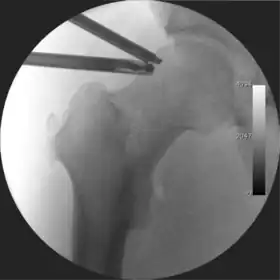

![]() Intraoperative fluoroscopic image during an arthroscopic resection of a cam lesion of the femur. The upper instrument is the arthroscope (viewing device), while the lower is the high-speed burr used for reshaping the bone. |

The procedure is performed with the patient asleep (general anaesthetic) or under spinal anaesthesia. There are two widely used methods, one with the patient on their back (supine) and the other on their side (lateral decubitus). Which is used is down to the surgeon's preference. To gain access to the central compartment of the hip joint (between the ball and socket), traction is applied to the affected leg after placing the foot into a special boot. (See fig. 2) There is specifically designed equipment for this, although some surgeons use a 'traction table', initially designed to help in the operative fixation of broken thigh and lower leg bones. The amount of traction (or pull) needed is assessed with the help of fluoroscopy (low-dose portable x-ray). (See fig. 3) It is usually not possible to distract the ball from the socket with traction alone by more than a few millimetres. Once the surgeon is happy that they will be able to gain access to the hip joint (i.e. the ball will distract from the socket by a small amount), the patient is then painted with antiseptic and the surgical drapes applied.

The next step is to insert a fine needle under x-ray guidance into the hip joint. This breaks the 'suction seal' of the joint and allows further distraction if necessary (see fig 4). The surgeon wishes to see the ball move out the socket by approximately 1 cm, so that access to the hip joint can be achieved with minimal risk of damage to the joint surfaces. Most surgeons will inject fluid into the joint at this stage, again to ensure that there is enough space between the ball and socket for safe instrument access. This needle is then removed. The next step is placement of the 'portals', or the small holes made to pass instruments into the joint. This is achieved by again passing a fresh hollow needle into the joint under x-ray control, usually in a slightly different position. The reason for this is so the surgeon can ensure that the needle, and subsequent cannulae do not penetrate and damage the acetabular labrum or cartilage joint surfaces (see fig. 5). Again, surgeons will have their own preferences as to their preferred placement. Through this hollow needle, a long thin flexible guide wire is passed into the joint, and the needle is removed over it, leaving the guide wire in situ. A small cut in the skin is made around the wire, to allow for larger cannulae to be placed over the wire through the portal. The wire therefore guides the larger cannulae into the joint. The most common external diameters of cannulae used are between 4.5 and 5.5 mm. Once the surgeon is satisfied that the cannula is in the correct position, by a combination of feel and x-ray guidance, the guide wire can be withdrawn. Once the first portal is correctly placed, any further portals may be created once the camera is in position, to ensure that they are placed with minimal risk to the joint surfaces. This process can be repeated to gain as many points of entry to the hip joint as the surgeon requires, normally between two and four. Certain of these entry points will be used for the viewing arthroscope and others for operating instruments.